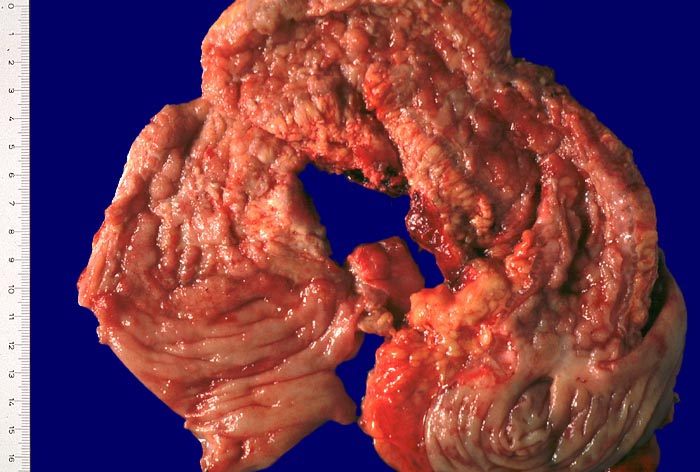

Makroskopisch typisch sind oberflächliche aphthöse Ulzera, gartenschlauchartige Strikturen im Dünn- und Dickdarm mit segmental verdickter und fibrosierter Darmwand, intramurale Abszesse, entzündliche Konglomerattumoren und verbackene Darmschlingen mit Fistelbildungen. Häufiger im Dünndarm als im Dickdarm findet sich das klassiche Pflastersteinrelief der Schleimhaut aufgrund rissförmiger Ulzera zwischen ödematösen Schleimhautarealen (> 369) Granulationsgewebspolypen oder Pseudopolypen (erhaltene Schleimhautinseln in Ulkusarealen) (> 408) finden sich beim Crohn seltener als bei der Colitis ulcerosa.

Die Verteilung der Läsionen im Darm ist sowohl makrokopisch (> 2884) als auch mikroskopisch (> 656) (> 409) diskontinuierlich und herdförmig ausgeprägt. Im Gegensatz zur Colitis ulcerosa können beim Morbus Crohn nicht nur das Kolon, sondern sämtliche Abschnitte des Gastrointestinaltraktes befallen sein. Am häufigsten ist das terminale Ileum zusammen mit dem Kolon befallen.